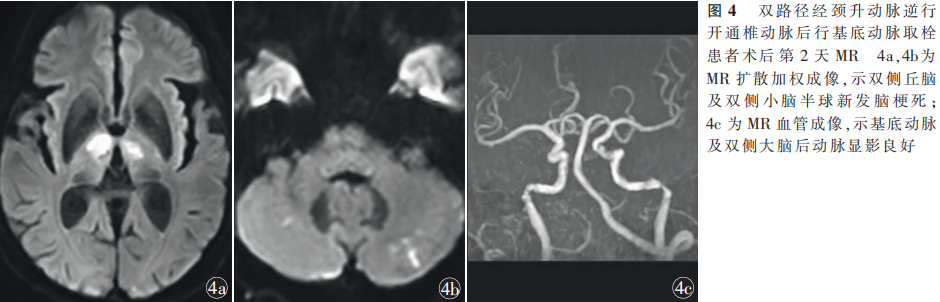

男,76岁,因“意识不清10h”于2022年8月5日18:12入住山东第二医科大学附属临沂市人民医院神经内科。患者于入院前10h突然出现意识不清,呼唤无反应,疼痛刺激可见皱眉,无发热、呕吐、肢体抽搐、大小便失禁。15:44于当地医院就诊,行脑血管造影见右侧椎动脉非优势,左侧椎动脉开口闭塞,诊断椎动脉闭塞性脑梗死,尝试行椎动脉机械取栓未成功,遂转入我院。患者既往高血压病史10年,平素不规律服药治疗;否认糖尿病、冠心病、卒中史。卒中门诊神经系统体格检查:浅昏迷,言语不合作,双侧眼球居中,双侧瞳孔直径3mm,对光反射灵敏;四肢肌力0级,四肢肌张力减低,双侧Babinski征阳性,美国国立卫生研究院卒中量表(NIHSS)评分31分;头部CT血管成像(CTA)、CT灌注示基底动脉尖闭塞(图1a),双侧小脑、脑干低灌注,存在较大面积缺血半暗带(图1b),诊断为脑梗死、基底动脉闭塞。拟行急诊血管内介入治疗。患者于2022年8月5日18:55全身麻醉后穿刺右侧股动脉,置入8F动脉鞘,送入5F单弯导管行双侧锁骨下动脉造影,示右侧椎动脉非优势(图2a),左侧椎动脉开口闭塞,未见明显残端,左侧颈升动脉代偿椎动脉颅内段显影,基底动脉显影差(图2b,2c),左侧颈总动脉造影示后交通开放,代偿大脑后动脉显影(图2d);单弯导管超选左侧锁骨下动脉,利用synchro2微导丝(0.014英寸×300cm;1英寸=2.54cm; Stryker,美国)尝试通过闭塞的左侧椎动脉,尝试数次未成功,遂将单弯导管超选左侧甲状颈干,造影示左侧颈升动脉代偿椎动脉颅内段,且椎动脉V2段可见逆向显影(图3a),动脉尖闭塞(图3b)。通过单弯导管送入synchro2微导丝+基底SL-10微导管(0.017英寸×150cm;Stryker,美国),通过左侧颈升动脉与椎动脉吻合口将微导丝送入椎动脉,同时逆行寻找椎动脉开口,成功将微导丝通过闭塞的椎动脉送至左侧锁骨下动脉(图3c);交换2mm×15mm颅内球囊扩张导管(普微森医疗科技有限公司),于椎动脉开口定位后加压至12个标准大气压扩张1次(图3d),球囊扩张过程中可见“束腰征”。此时穿刺左侧桡动脉,置入6F桡动脉鞘,沿鞘送入6F Envoy导引导管(0.070英寸;Cordis,美国)至左侧椎动脉开口附近,沿导引导管送入pilot50微导丝(0.014英寸×190cm;Abbott,美国)+ 3mm×20mm颅内球囊扩张导管(普微森医疗科技有限公司),以synchro2微导丝为参照顺向超选左侧椎动脉(图3e),pilot50微导丝顺利送至V2段;跟进球囊,于椎动脉开口加压至12个标准大气压扩张1次(图3f);撤出逆向synchro2微导丝,以pilot50微导丝及3mm×20mm颅内球囊扩张导管为支撑跟进导引导管至V2段;经6F导引导管造影证实基底动脉尖闭塞,断端平齐(图3g);撤出微导丝及球囊,沿导引导管送入synchro2微导丝+ prowler select plus微导管 (0.021英寸× 150cm;Cordis,美国),通过基底动脉闭塞段送至左侧大脑后动脉P2段,冒烟证实真腔;沿微导管置入trevoXP取栓支架(4mm×20mm;Stryker,美国)于闭塞段释放(图3h),支架锚定置入tracLine远端通路导管(5F;禾木生物工程有限公司)至闭塞段,负压下拉栓1次,见多枚血栓取出,即刻造影示基底动脉恢复前向血流,改良脑梗死溶栓(modified thrombolysis in cerebral infarction, mTICI)分级3级(图3i,3j)。穿刺至首次血管再通时间115min。回撤导引导管,造影示左侧椎动脉开口重度狭窄,狭窄率90%(图3k),给予替罗非班0.5mg/h静脉泵入抗血小板聚集,随后于椎动脉开口置入SD支架(4mm×19mm;波科,美国;图3l),即刻造影示支架完全覆盖病变,贴壁良好,基底动脉及双侧大脑后动脉血流通畅(图3m)。静脉泵入替罗非班48h后改阿司匹林联合氯吡格雷抗血小板聚集治疗并维持90d。术后第2天复查头部MR,扩散加权成像示双侧丘脑及双侧小脑半球新发脑梗死(图4a,4b),MR血管成像(MRA)示基底动脉及双侧大脑后动脉血流通畅(图4c)。术后4d患者病情稳定,神经系统体格检查:意识清楚,构音障碍,双侧瞳孔等大等圆,直径3mm,对光反射灵敏,双侧鼻唇沟对称,左侧肢体肌力Ⅳ级,右侧肢体肌力Ⅴ级,左侧Babinski征阳性,NIHSS评分5分;无穿刺点血肿、颅内出血等并发症。于2022年8月12日出院。术后90d电话随访,mRS评分1分。